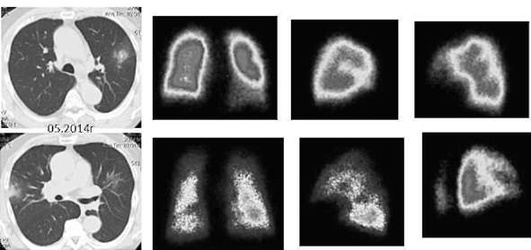

Проведенное нами динамическое исследование КТ-паттернов у 42 больных ЭТА показало трансформацию отдельных типов интерстициальных пневмоний по мере прогрессирования патологического процесса в фиброзную НСИП или ОИП (рис. 2.30), что подтверждает объединительную концепцию интерстициальных пневмоний вне зависимости от этиологического фактора, которые являются не отдельными нозологическими формами, а стадиями течения фиброзирующего процесса в легких (Илькович М.М., Новикова Л.Н., 2018; Орлова Г.П. и др., 2019).

Исследование легочно-сердечной гемодинамики. При эходоплеркардиографии отмечается увеличение систолического давления в легочной артерии за счет повышения общего легочного сопротивления по отношению к нормальным величинам. Наличие нарушений гемодинамики малого круга кровообращения подтверждается данными сцинтиграфии легких с 99m[Tc], указывающими на диффузные нарушения перфузии разной степени выраженности. Перфузионная сцинтиграфия позволяет выявить осложнение альвеолита тромбоэмболией мелких ветвей легочной артерии. Так, при амиодарониндуцированном ЭТА в 31,1% случаев могут выявляться субплевральные участки консолидации легочной ткани, подозрительные на присоединение тромбэмболии мелких ветвей легочной артерии (Яковлева Н.С. и др., 2019). В этих случаях диагностика тромбоэмболии по данным КТ затруднена на фоне текущего альвеолита или распространенных фиброзных изменений. По нашим данным, из 16,7% больных только у 3,3% ТЭЛА была выявлена при ангиоКТ, а у 13,4% больных признаки тромбоэмболии мелких ветвей легочной артерии выявлялись при перфузионной сцинтиграфии с Тс-99-МАА (рис. 2.31).